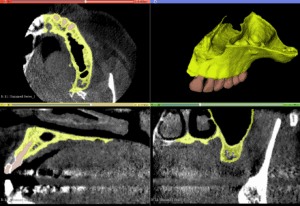

3D printing of bone

precise 3D printed representation of the bone morphology

Sinus Membrane

The exact anatomy and thickness of the sinus membrane can be also printed together with the bone

Final life-size model

A precise realistic model of all tissue is then made available for rehearsal of any surgical techniques

A Challenging surgical case with a complex of vertical and horizontal septa in the posterior sinus. Segmentation of the 3D radiographical and optical data and 3D printing in multiple layers from AMMA Ltd Hong Kong, has allowed for an accurate representation of the anatomy where multiple surgical access approaches were tested.